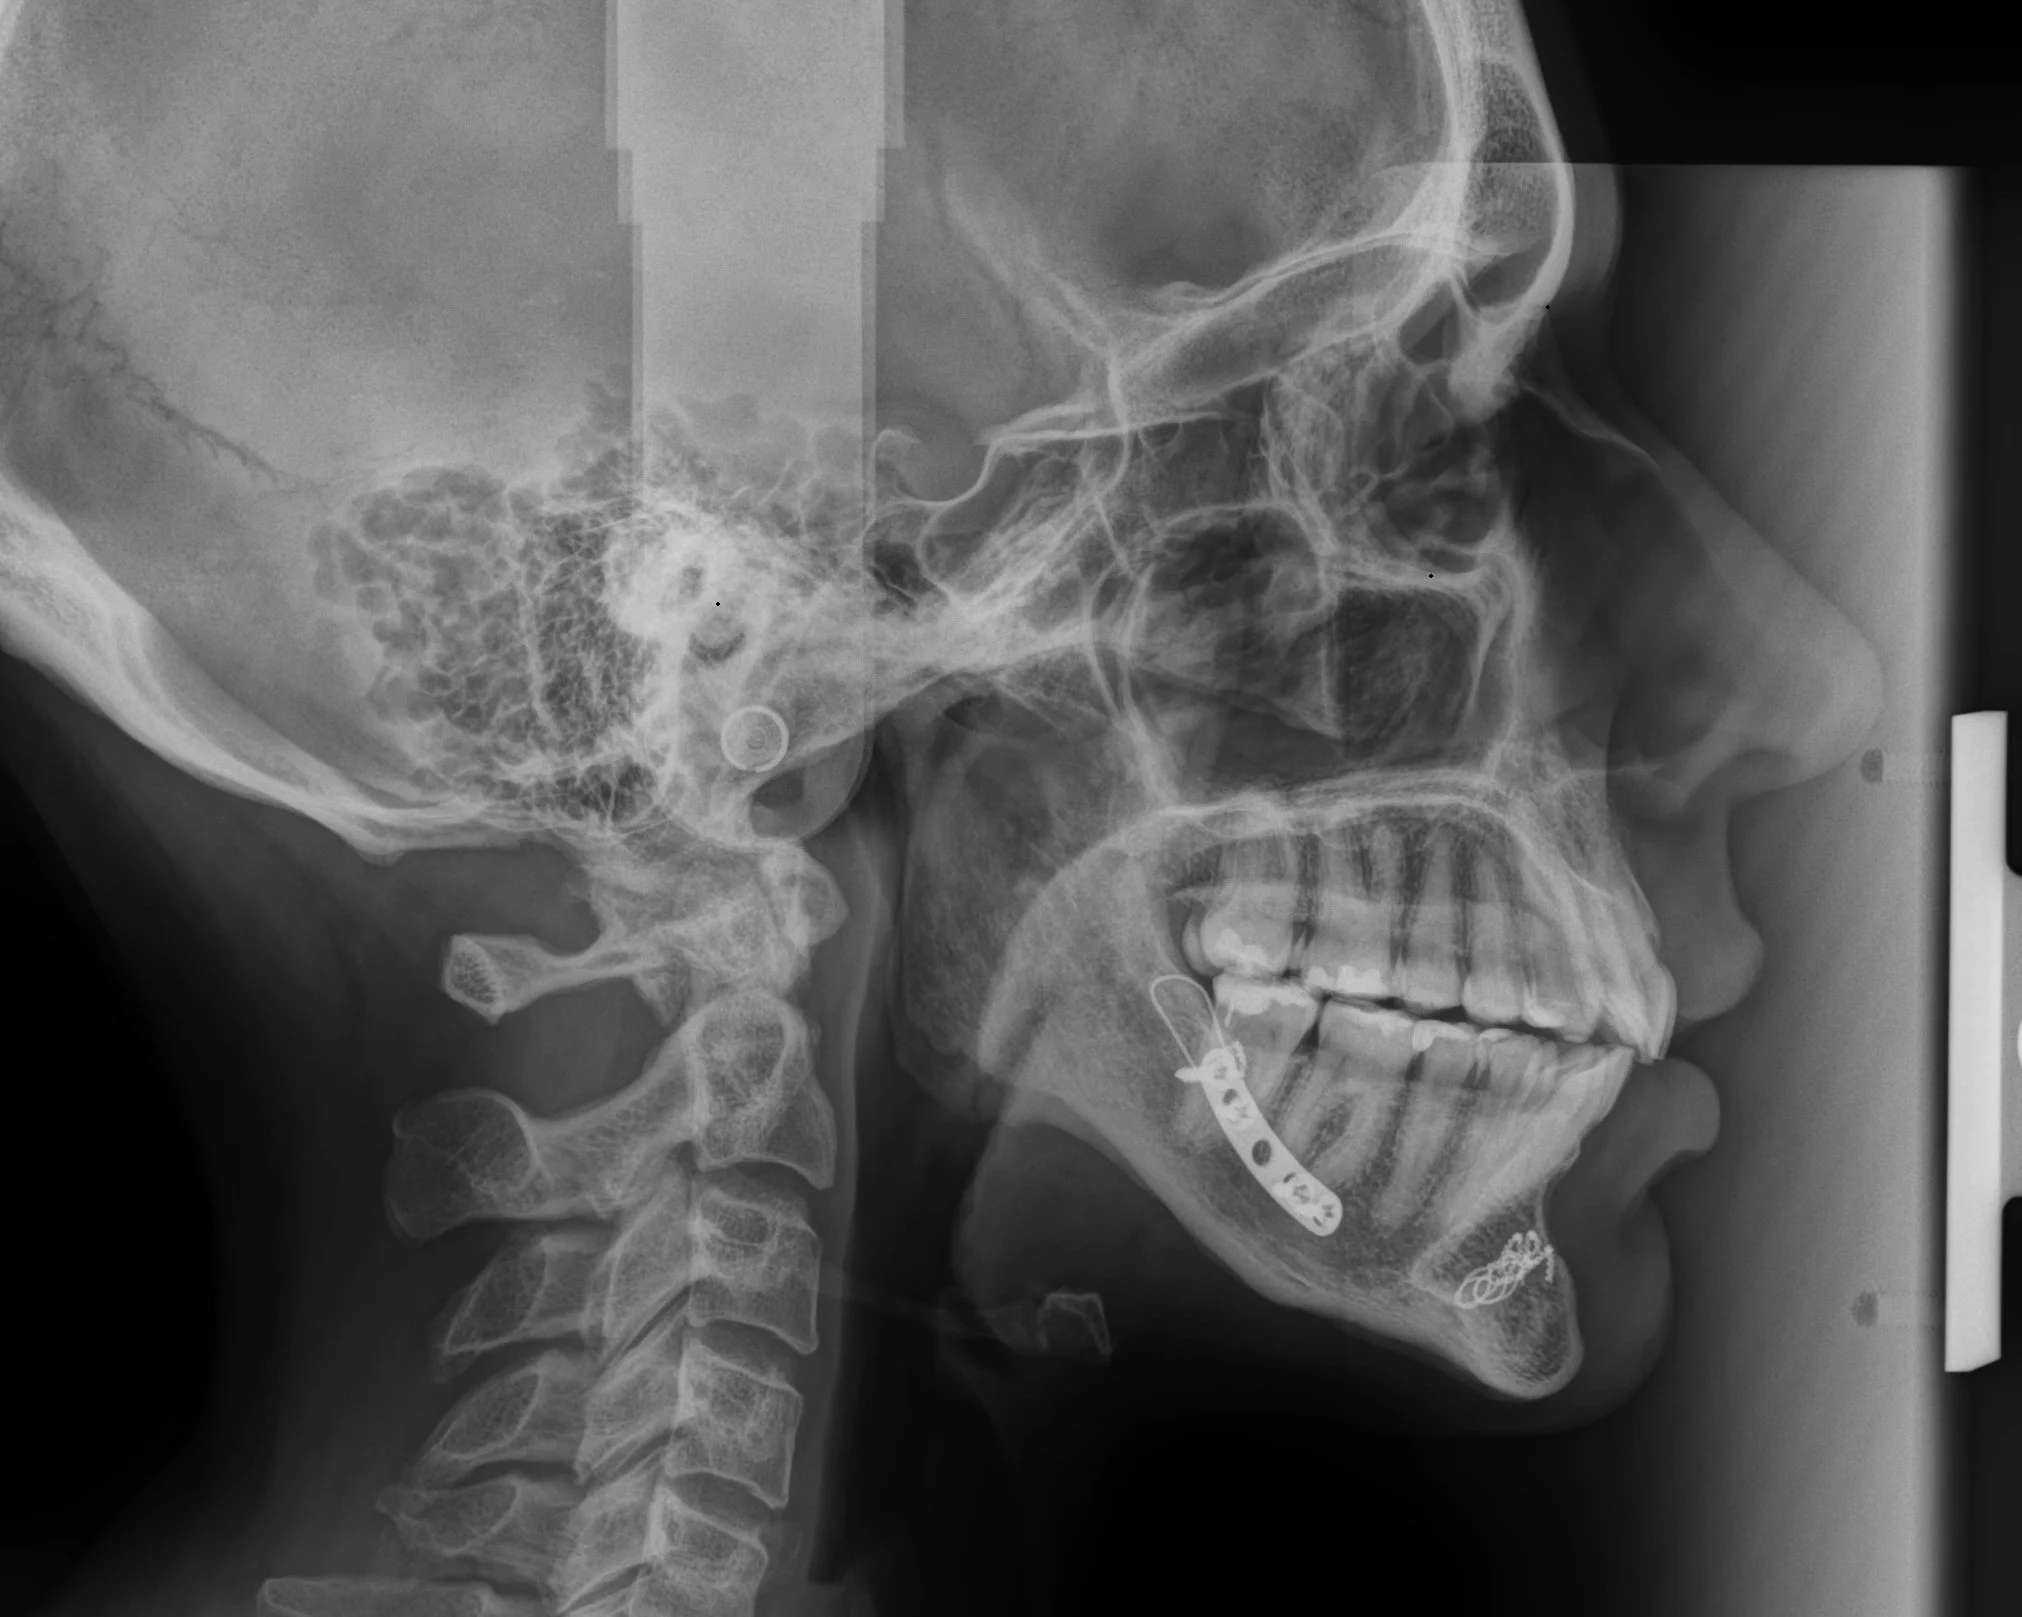

1988 - Jaw Surgery

CT Scans

X-Rays

Testing of electrical currents in Maria’s body showed they were the highest the doctor had seen into the extreme levels.

Testing of the metal in Maria’s jaw from a childhood surgery also tested at the same levels for electrical current.

The future involves investigating heavy metal toxicity caused by metal implants in Maria’s jaw which were placed 37 years ago. Blood testing in Tennessee and intake appointments are already happening for clinics in either Switzerland or Costa Rica. What happens with metal implants? Surgery locations are either TRYBE in Costa Rica or Swiss Biohealth. https://www.swiss-biohealth.com/en unless the Lord guides us elsewhere.

Galvanism occurs in the body when electrical currents are generated inside the body by dissimilar metals like titanium, stainless steel, and amalgam. Nickel hypersensitivity and trace contaminants can occur. Post-surgical complications are likely present which create galvanism as well as chronic pain, and neurological symptoms linked to metal-based implants.

About Metal Plates and Systemic Impact

Metal hardware placed decades ago—especially in the 1980s—was commonly made from alloys that are no longer considered optimal from a biological standpoint. Over time, these materials can contribute to:

• Chronic local inflammation

• Galvanic currents and EMF sensitivity

• Immune system overstimulation

• Disruption of autonomic nervous system signaling

• Heavy metal burden or bio-incompatibility responses

While not every patient reacts the same way, the jaw is a highly neurological, vascular, and lymphatic area, meaning any chronic stressor there can have wide systemic effects.

Dr. Schroeder, a renown surgeon who operates the Metal Allergy & Reactions Institute, LLC', and has presented his findings to the FDA is a resource with great experience and visual evidence of metal-induced bioelectric disruption and case studies of patients with dramatic transformations with the removal of metal from the body, including the reversal of paralysis.

Dr. Schroeder is known and respected worldwide as an expert and lecturer on metal allergies, especially within the realm of surgical specialties. Dr. Schroeder speaks on many of his surgical miracle stories, often delivering patients with metal hypersensitivity from years and even decades of chronic pain virtually overnight, but also teaches us about galvanism: when dissimilar surgical metals act like a battery within the body, literally charging it with electric current, which also is a huge contributor to the faster speed of implant degradation and corrosion.